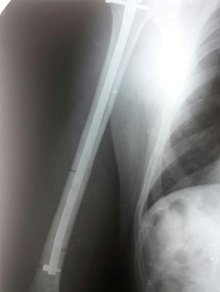

Перелом діалізу плечової кістки синтезований блокованим стержнем